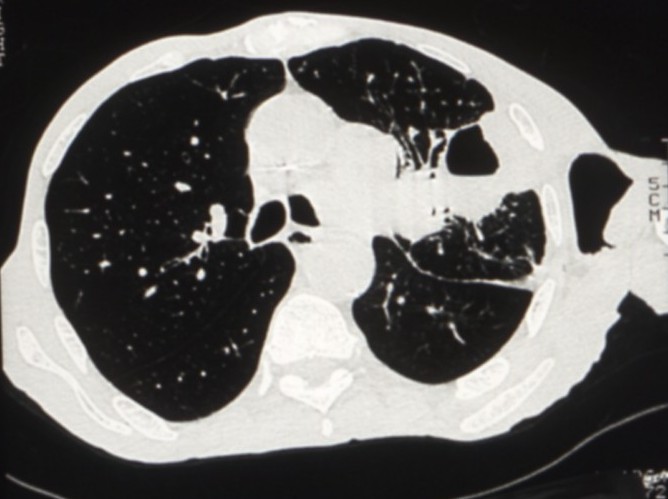

Cancers bronchiques